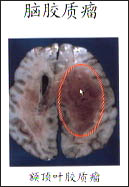

主持人:脑胶质瘤是一种什么样的疾病? 吴念曾:胶质细胞瘤生长在脑部组织里,没有完整的包膜,与正常脑组织呈犬牙交错并且是侵入性的生长,如图红圈中就是肿瘤发生的部位。脑胶质瘤可以发生在脑部的任何部位,如图这是一个脑胶质瘤好发部位示意图,这些部位分布了神经系统里面的主要神经和血管,人得了脑胶质瘤后就会影响到意识状态、肢体活动、语言状态等主要功能。